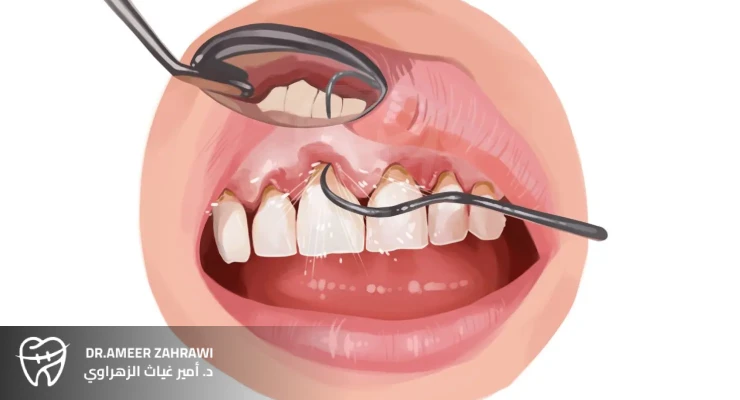

Deep dental cleaning, also known as scaling and root planing, is a specialized dental procedure that goes beyond regular cleanings to treat gum disease and support optimal oral health.This intensive treatment targets the areas beneath the gumline where plaque and tartar accumulate, causing inflammation and potentially leading to tooth loss if not addressed.During a deep dental cleaning, the dentist uses specialized instruments to remove these deposits from the tooth roots and smooth the root surfaces. This helps the gums reattach more effectively to the teeth, promotes healing, and reduces the risk of further damage.

Deep dental cleaning is a vital procedure for treating gum disease, preventing tooth loss, and improving overall oral health. By addressing the underlying cause of gingival inflammation and infection, deep cleaning helps patients maintain healthy gums and teeth, supporting a confident smile and better general health.